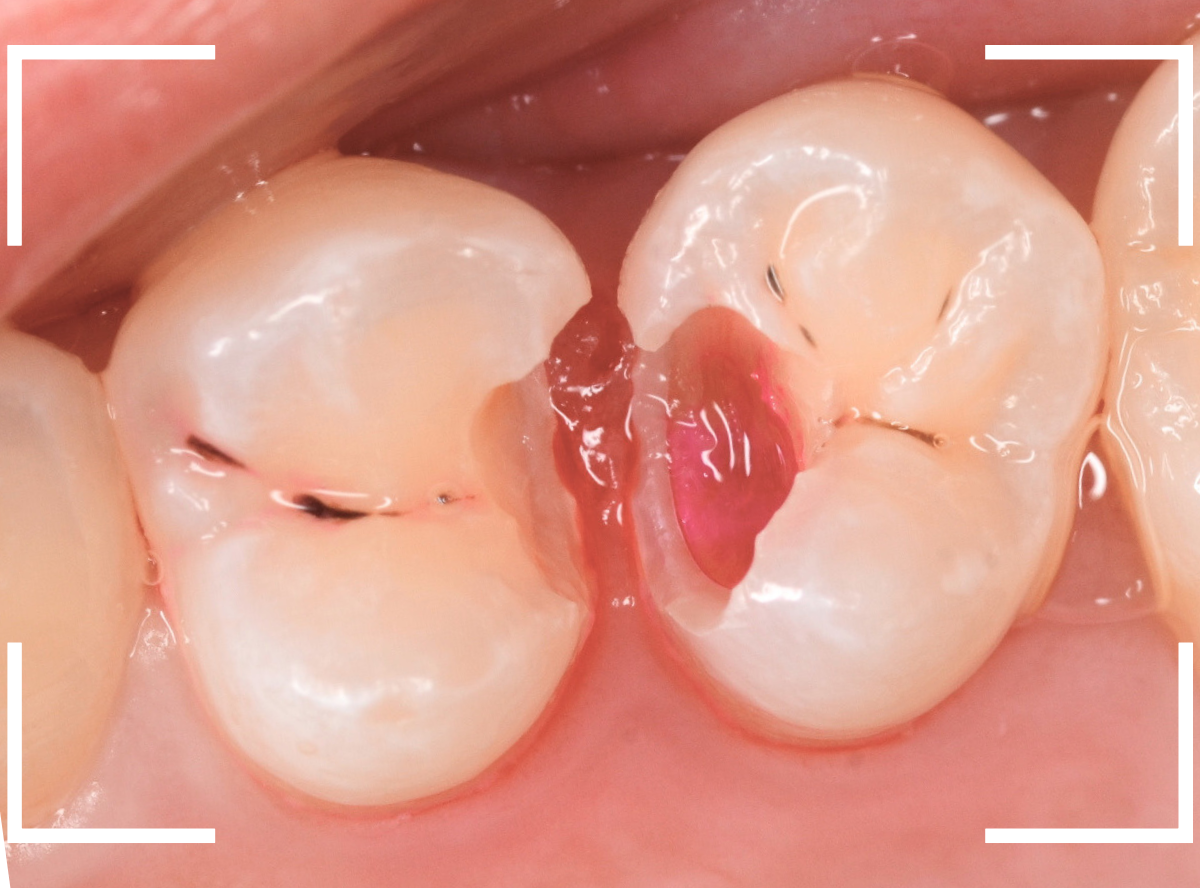

Case.23 歯のすきまから両側が大きな虫歯

「下の奥歯が痛む」という訴えで来院された患者さんのケースです。

目視でも、手前の奥歯がかけていて、中で虫歯が広がってるであろうことは予想できます。

ピンセットで歯を叩いてみても、手前の奥歯が痛むようです。

レントゲン写真で確認します。

青い線が神経、赤い線が虫歯の範囲です。

奥歯の方がより深い虫歯に見えますが、再度打診で確認したところ、やはり手前の奥歯が痛むそうです。

状況から、まず手前の奥歯から治療となりました。

麻酔をして、手前の奥歯のレジンを慎重に外します。

前に虫歯の治療をした時点で、神経スレスレの状態でしたので、削りすぎないように慎重にレジンを外さなければいけません。

レジンを外して、う蝕検知液で確認します。

レジンの中で虫歯が進行していたのがわかります。

慎重に全ての虫歯を除去しました。

何とか、神経が露出せずに済んでいます。

お薬をつめて、セメントで蓋をして経過観察します。